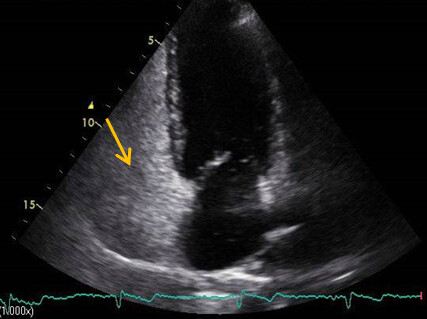

Um die Frage nach einem wirksamen Shunt zu präzisieren, erfolgte eine Rechtsherz-Echokardiografie mit Kontrastmittel (KM). Hierbei konnte sowohl in Ruhe als auch unter Valsalva ein Übertritt von Bubbles auf Vorhofebene dokumentiert werden (Abb. 1C / D). Unter Berücksichtigung der zurückhaltenden Einstellung der Patientin und der fehlenden neurologischen Residuen, die für keine gesicherte paradoxe Embolie sprachen, wurde eine Medikation mit ASS eingeleitet und die Patientin neurologisch wiederholt untersucht. Sie blieb bisher beschwerdefrei.

Abb. 4: Rechtsherz Eckokardiografie, Credit: Perings